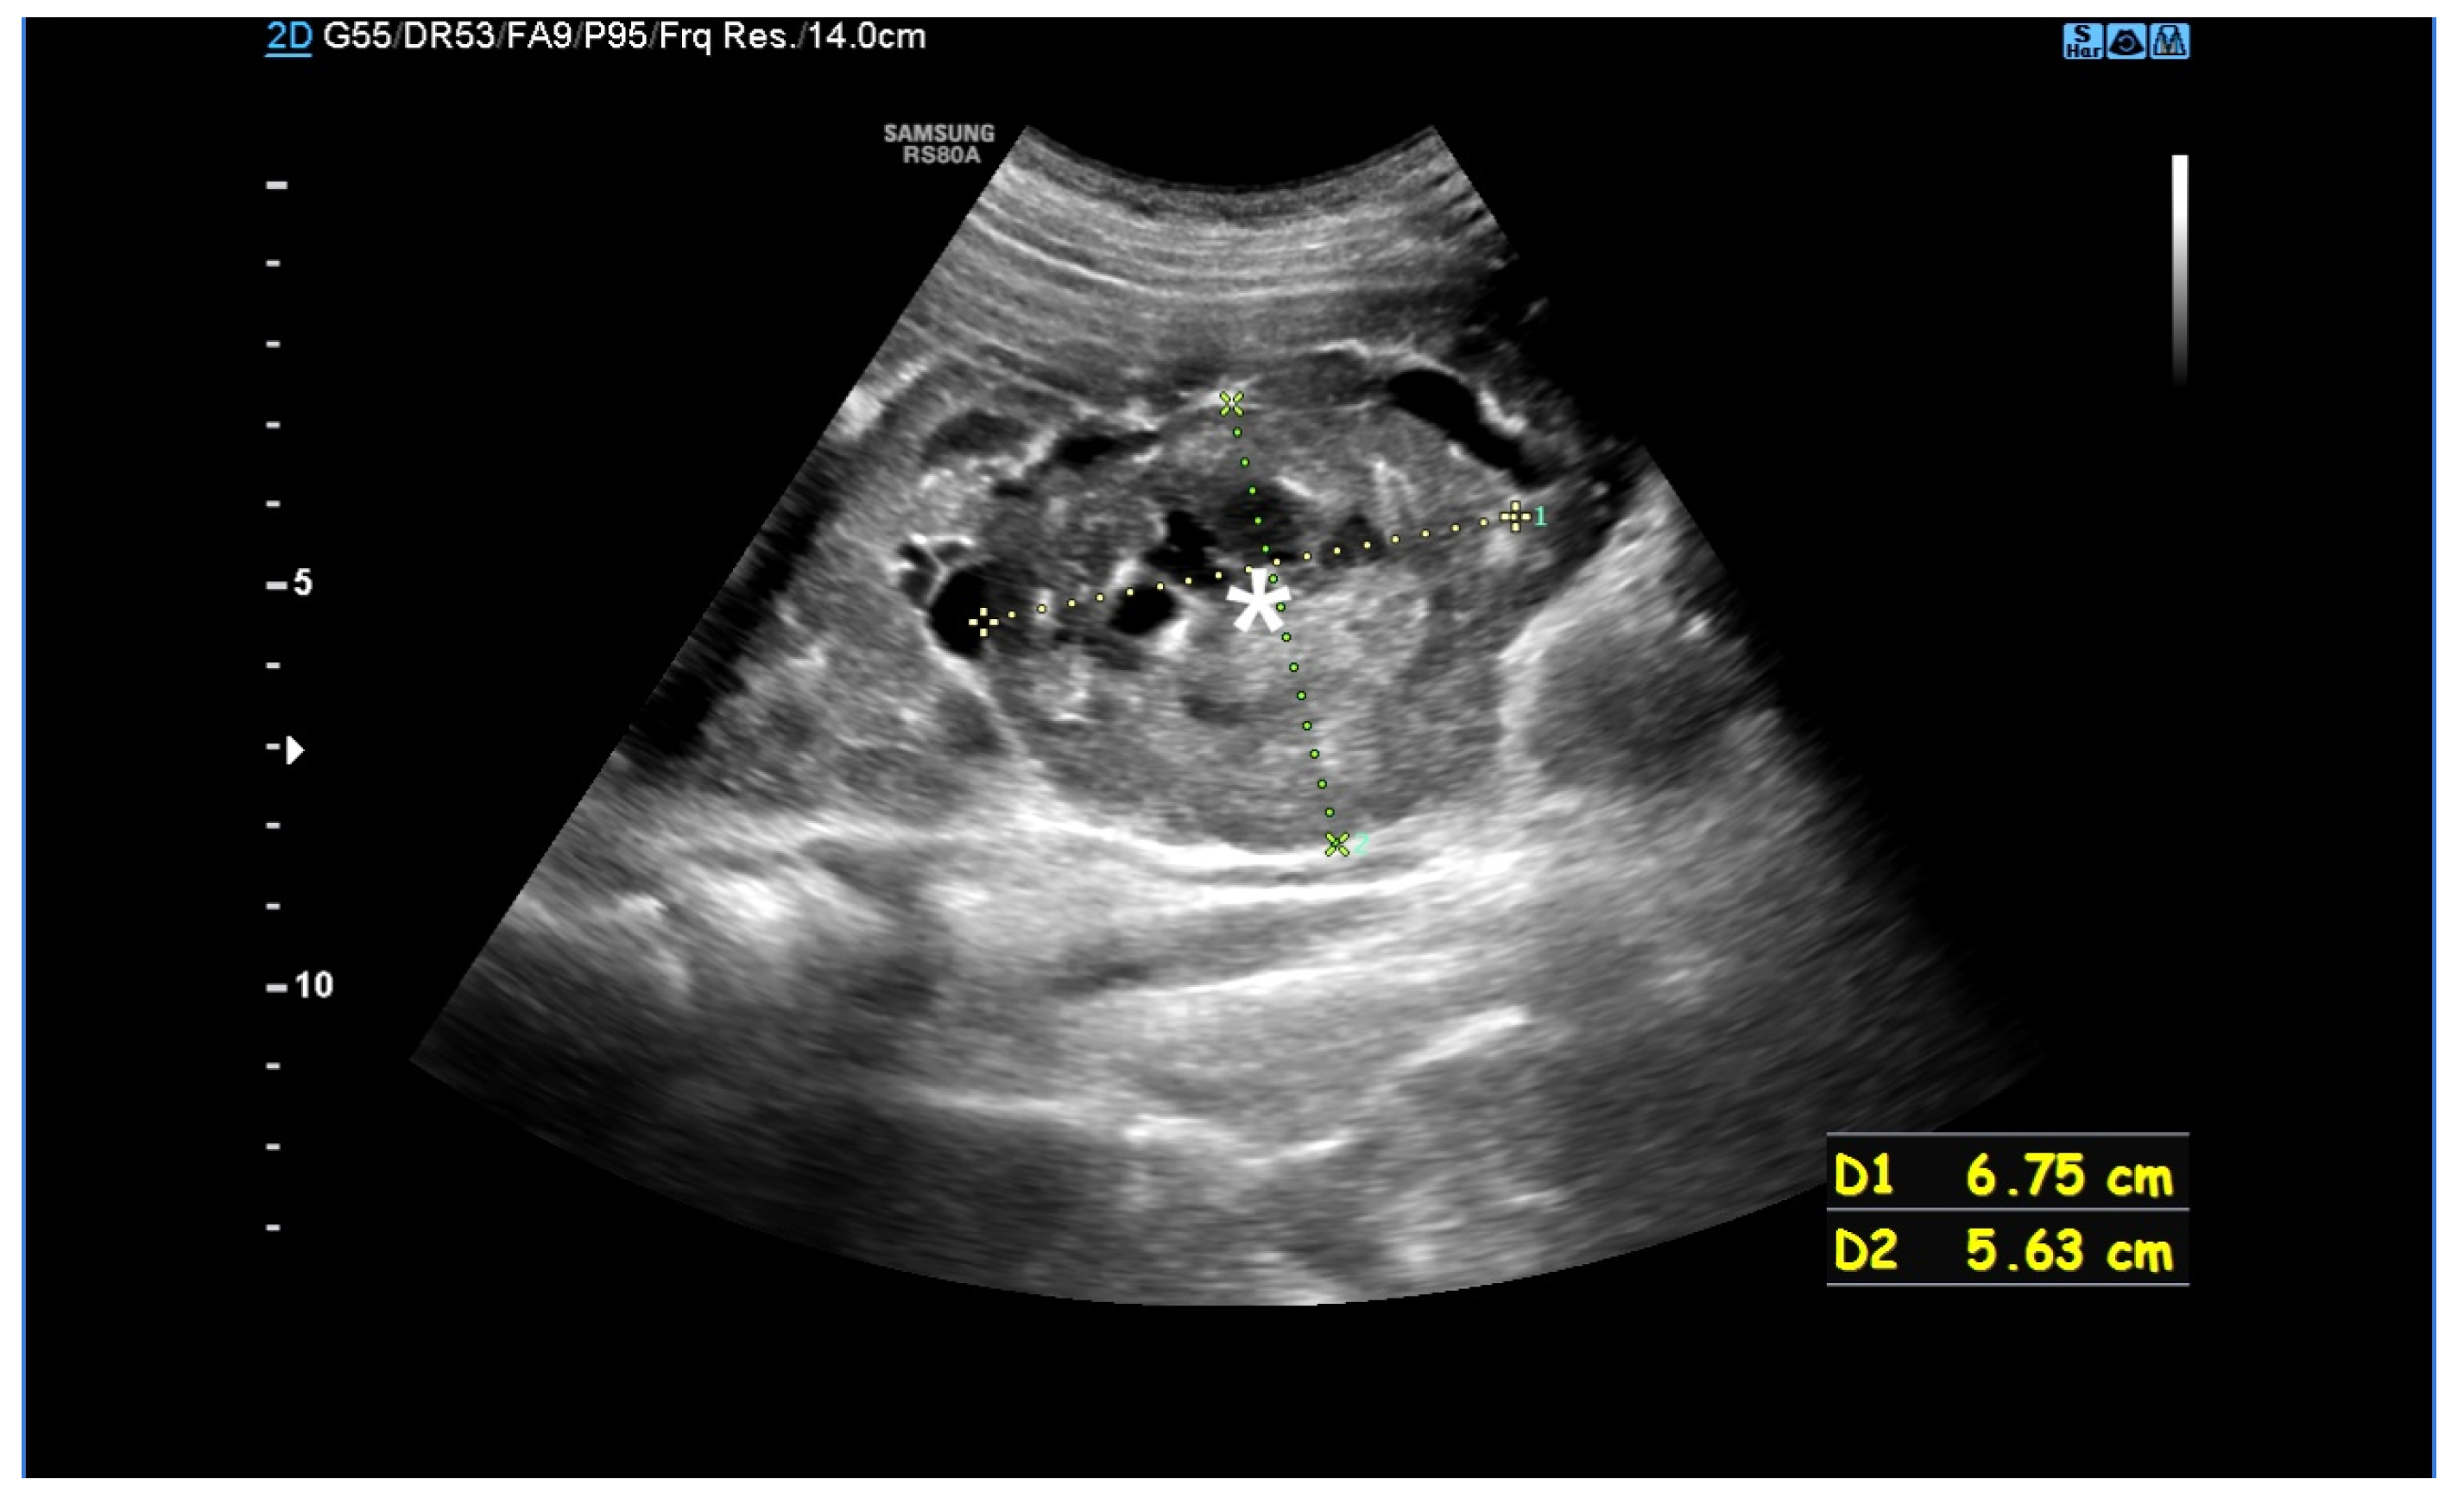

Figure 3. An MRI without (A) and with a contrasting agent (B) of a 3-year-old boy with a contiguous gene deletion syndrome involving TSC2/PKD1. Both kidneys are markedly enlarged, containing numerous thin-walled cysts of varying shapes. The remaining renal parenchyma is severely deformed.